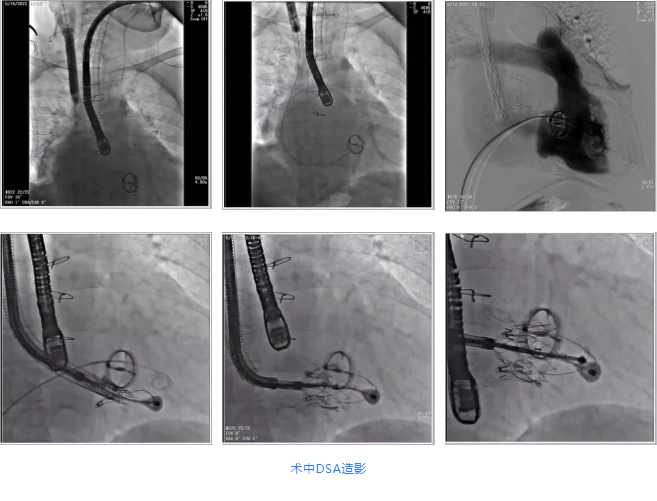

根據(jù)術(shù)前評(píng)估結(jié)果,郭應(yīng)強(qiáng)教授團(tuán)隊(duì)為患者量身定制了手術(shù)策略,決定使用LuX-Valve Plus經(jīng)血管三尖瓣置換系統(tǒng)開(kāi)展手術(shù)治療。手術(shù)在全麻下進(jìn)行,采用經(jīng)右側(cè)頸靜脈入路,在經(jīng)食道超聲和DSA的指引下調(diào)整輸送器角度以達(dá)到正確位置,勾住前瓣后逐步釋放盤(pán)片,盤(pán)片打開(kāi)后順利扎針,最終完成瓣膜植入,輸送器撤出。術(shù)后超聲提示人工三尖瓣同軸性良好,瓣架固定牢靠,無(wú)反流和瓣周漏,術(shù)后三尖瓣平均跨瓣壓差為1 mmHg。